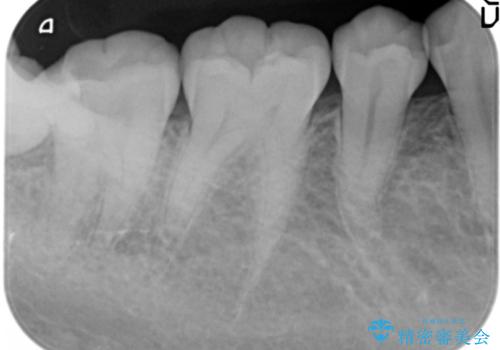

- 右下奥の強烈な痛み、腫れの改善を求めて来院されました。

視診・X線写真より親知らず周囲の進行した炎症発生、倒れた親知らずに起因する歯の神経に達する深い虫歯が見られました。

親知らずは抜去を行い、手前の第2大臼歯は根管治療後セラミッククラウンの製作を行います。